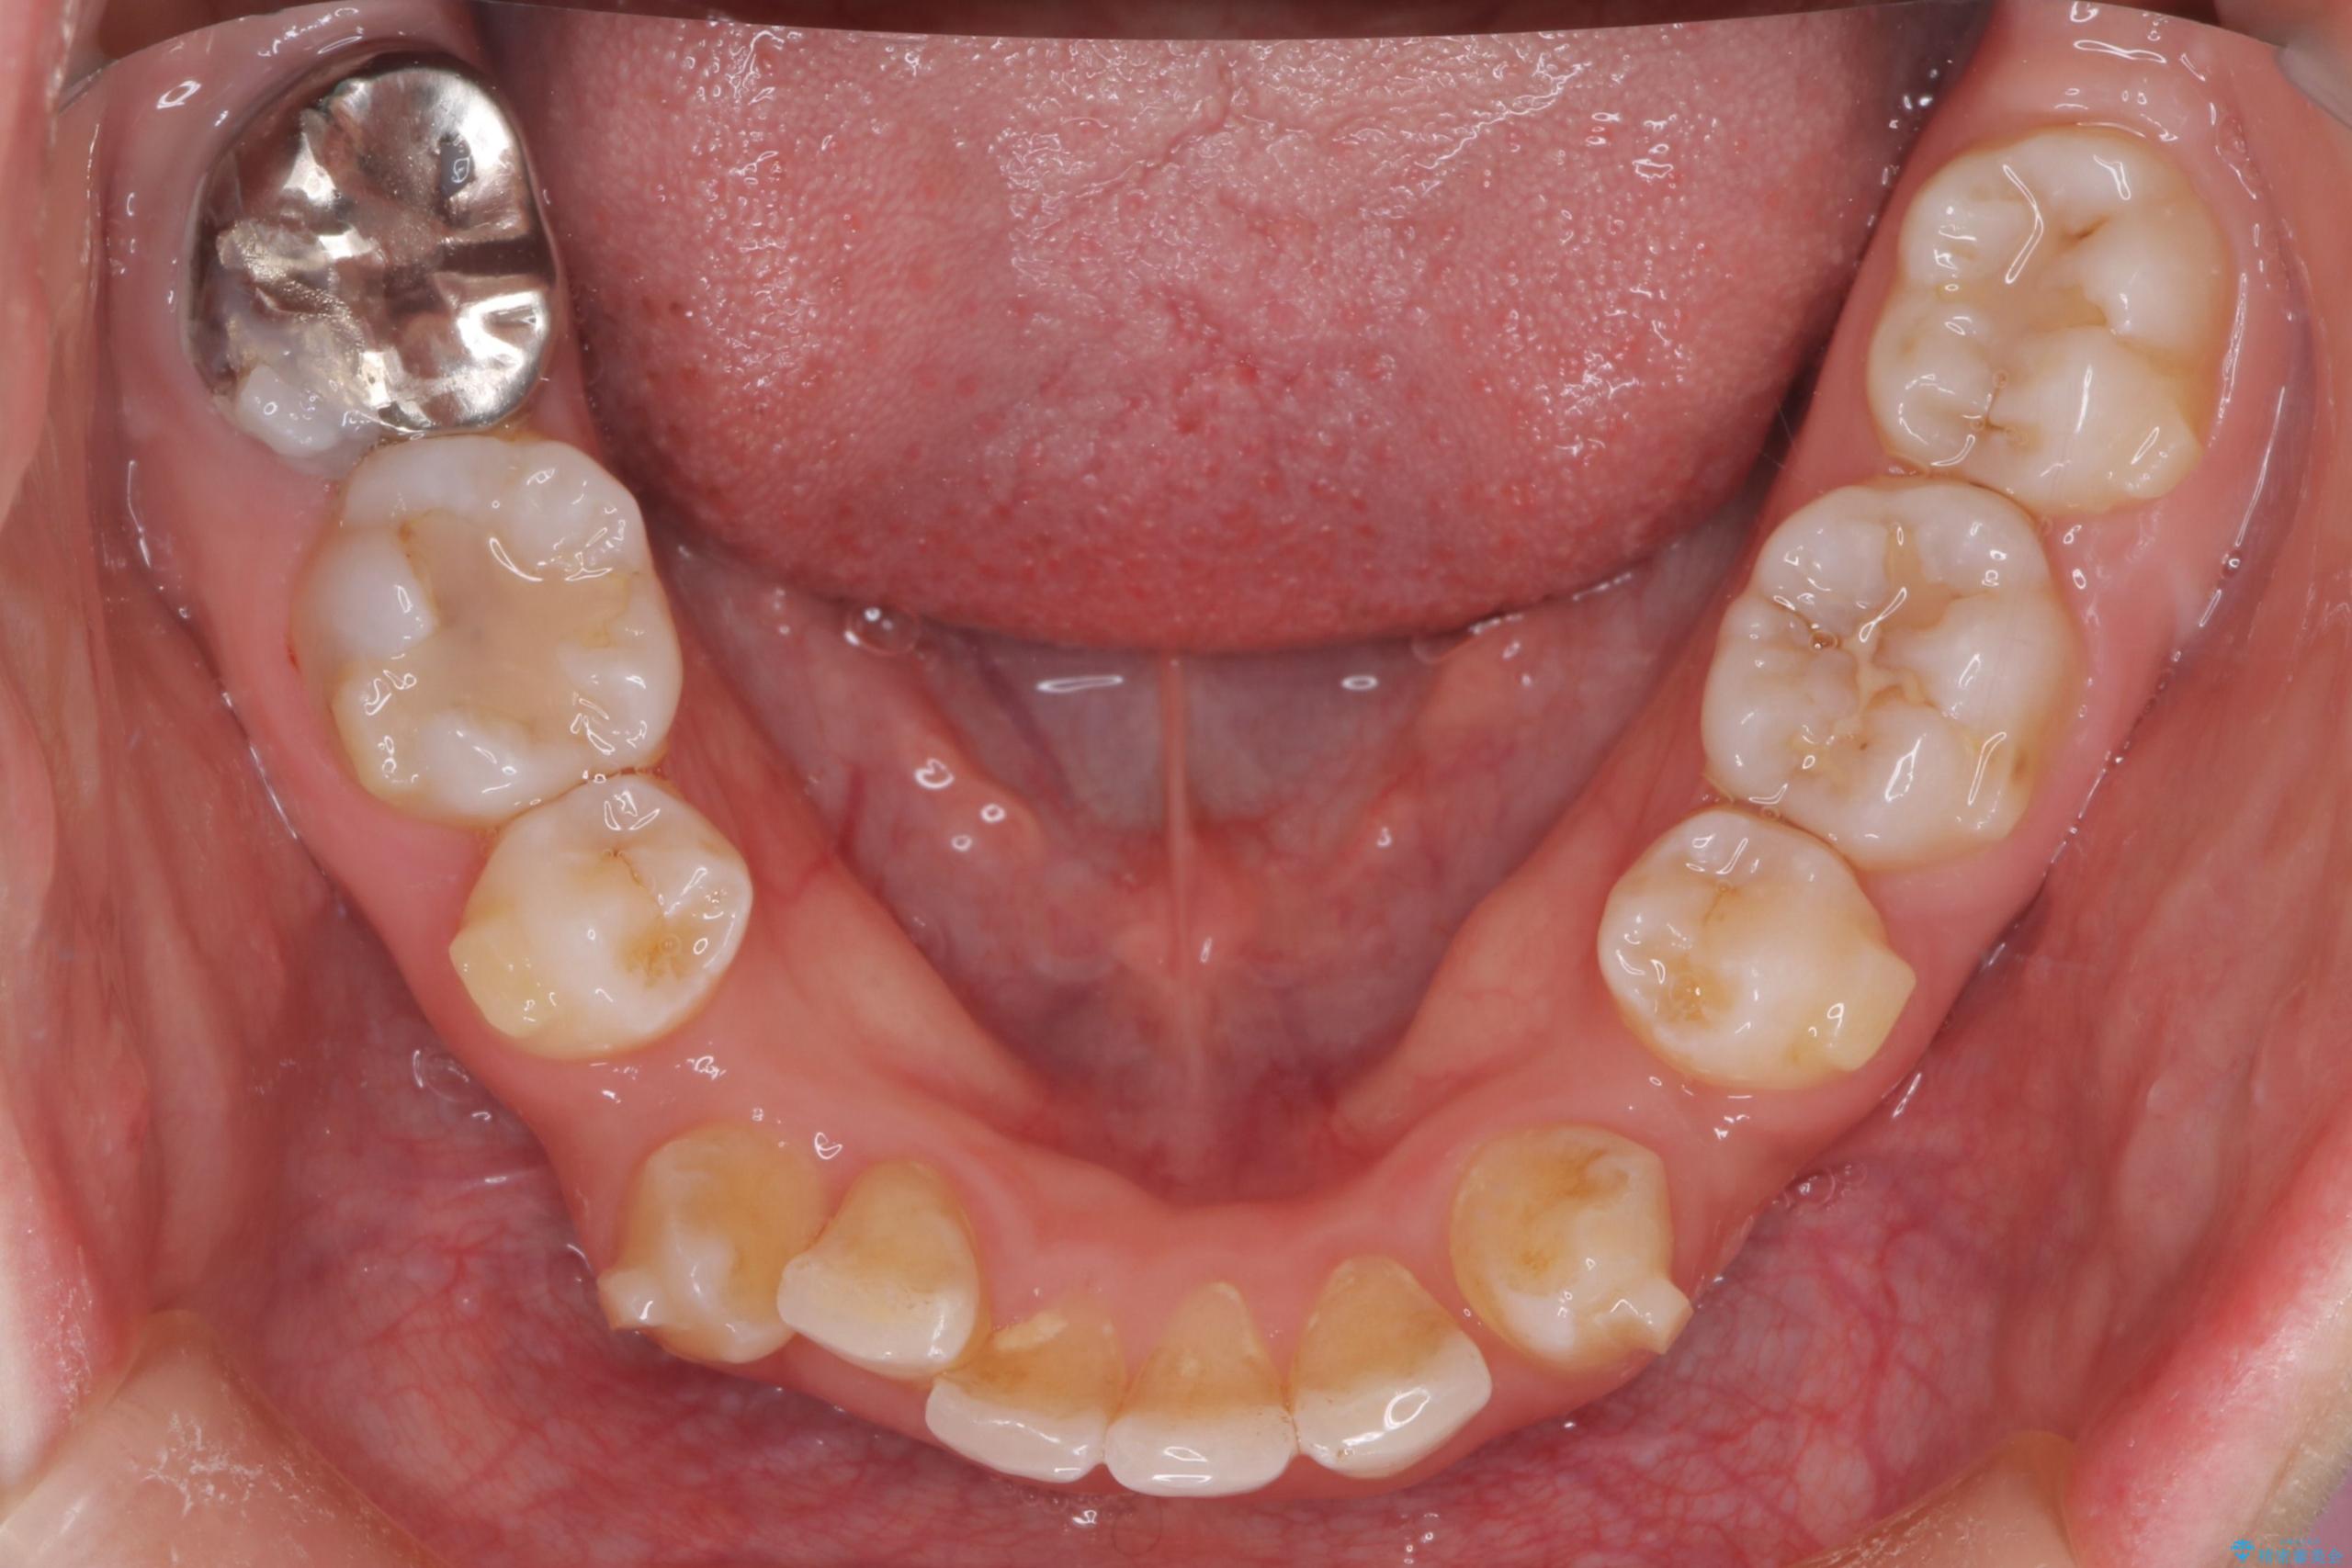

- 前歯から奥歯にかけて歯の重なりが激しい歯のがたつき(重度叢生)を主訴にご来院されました。精密検査の結果、歯が並ぶスペースが大幅に不足しており、歯並びを整え、口元を美しく引っ込めるためには、スペースの確保が必要と診断しました。そこで、上下左右の第一小臼歯(4番目の歯)を計4本抜歯し、そのスペースを利用して歯並び全体を整える抜歯矯正の治療計画を立案。装置には、透明で目立たないインビザラインを採用し、審美性と治療効果の両立を目指しました。

今回の治療では、重度の叢生を改善するため、まず計画通り上下左右4本の小臼歯を抜歯し、歯を並べるための十分なスペースを確保しました。装置には透明で取り外し可能なインビザラインを使用。抜歯によってできたスペースを最大限に活用し、マウスピースを定期的に交換しながら、デコボコを解消しつつ、前歯を効果的に後退させました。

治療の結果、長年の悩みであった重度の歯のがたつきが解消され、口元の突出感も改善。機能的にも安定し、審美的にも美しい、理想的な歯並びを獲得していただけました。